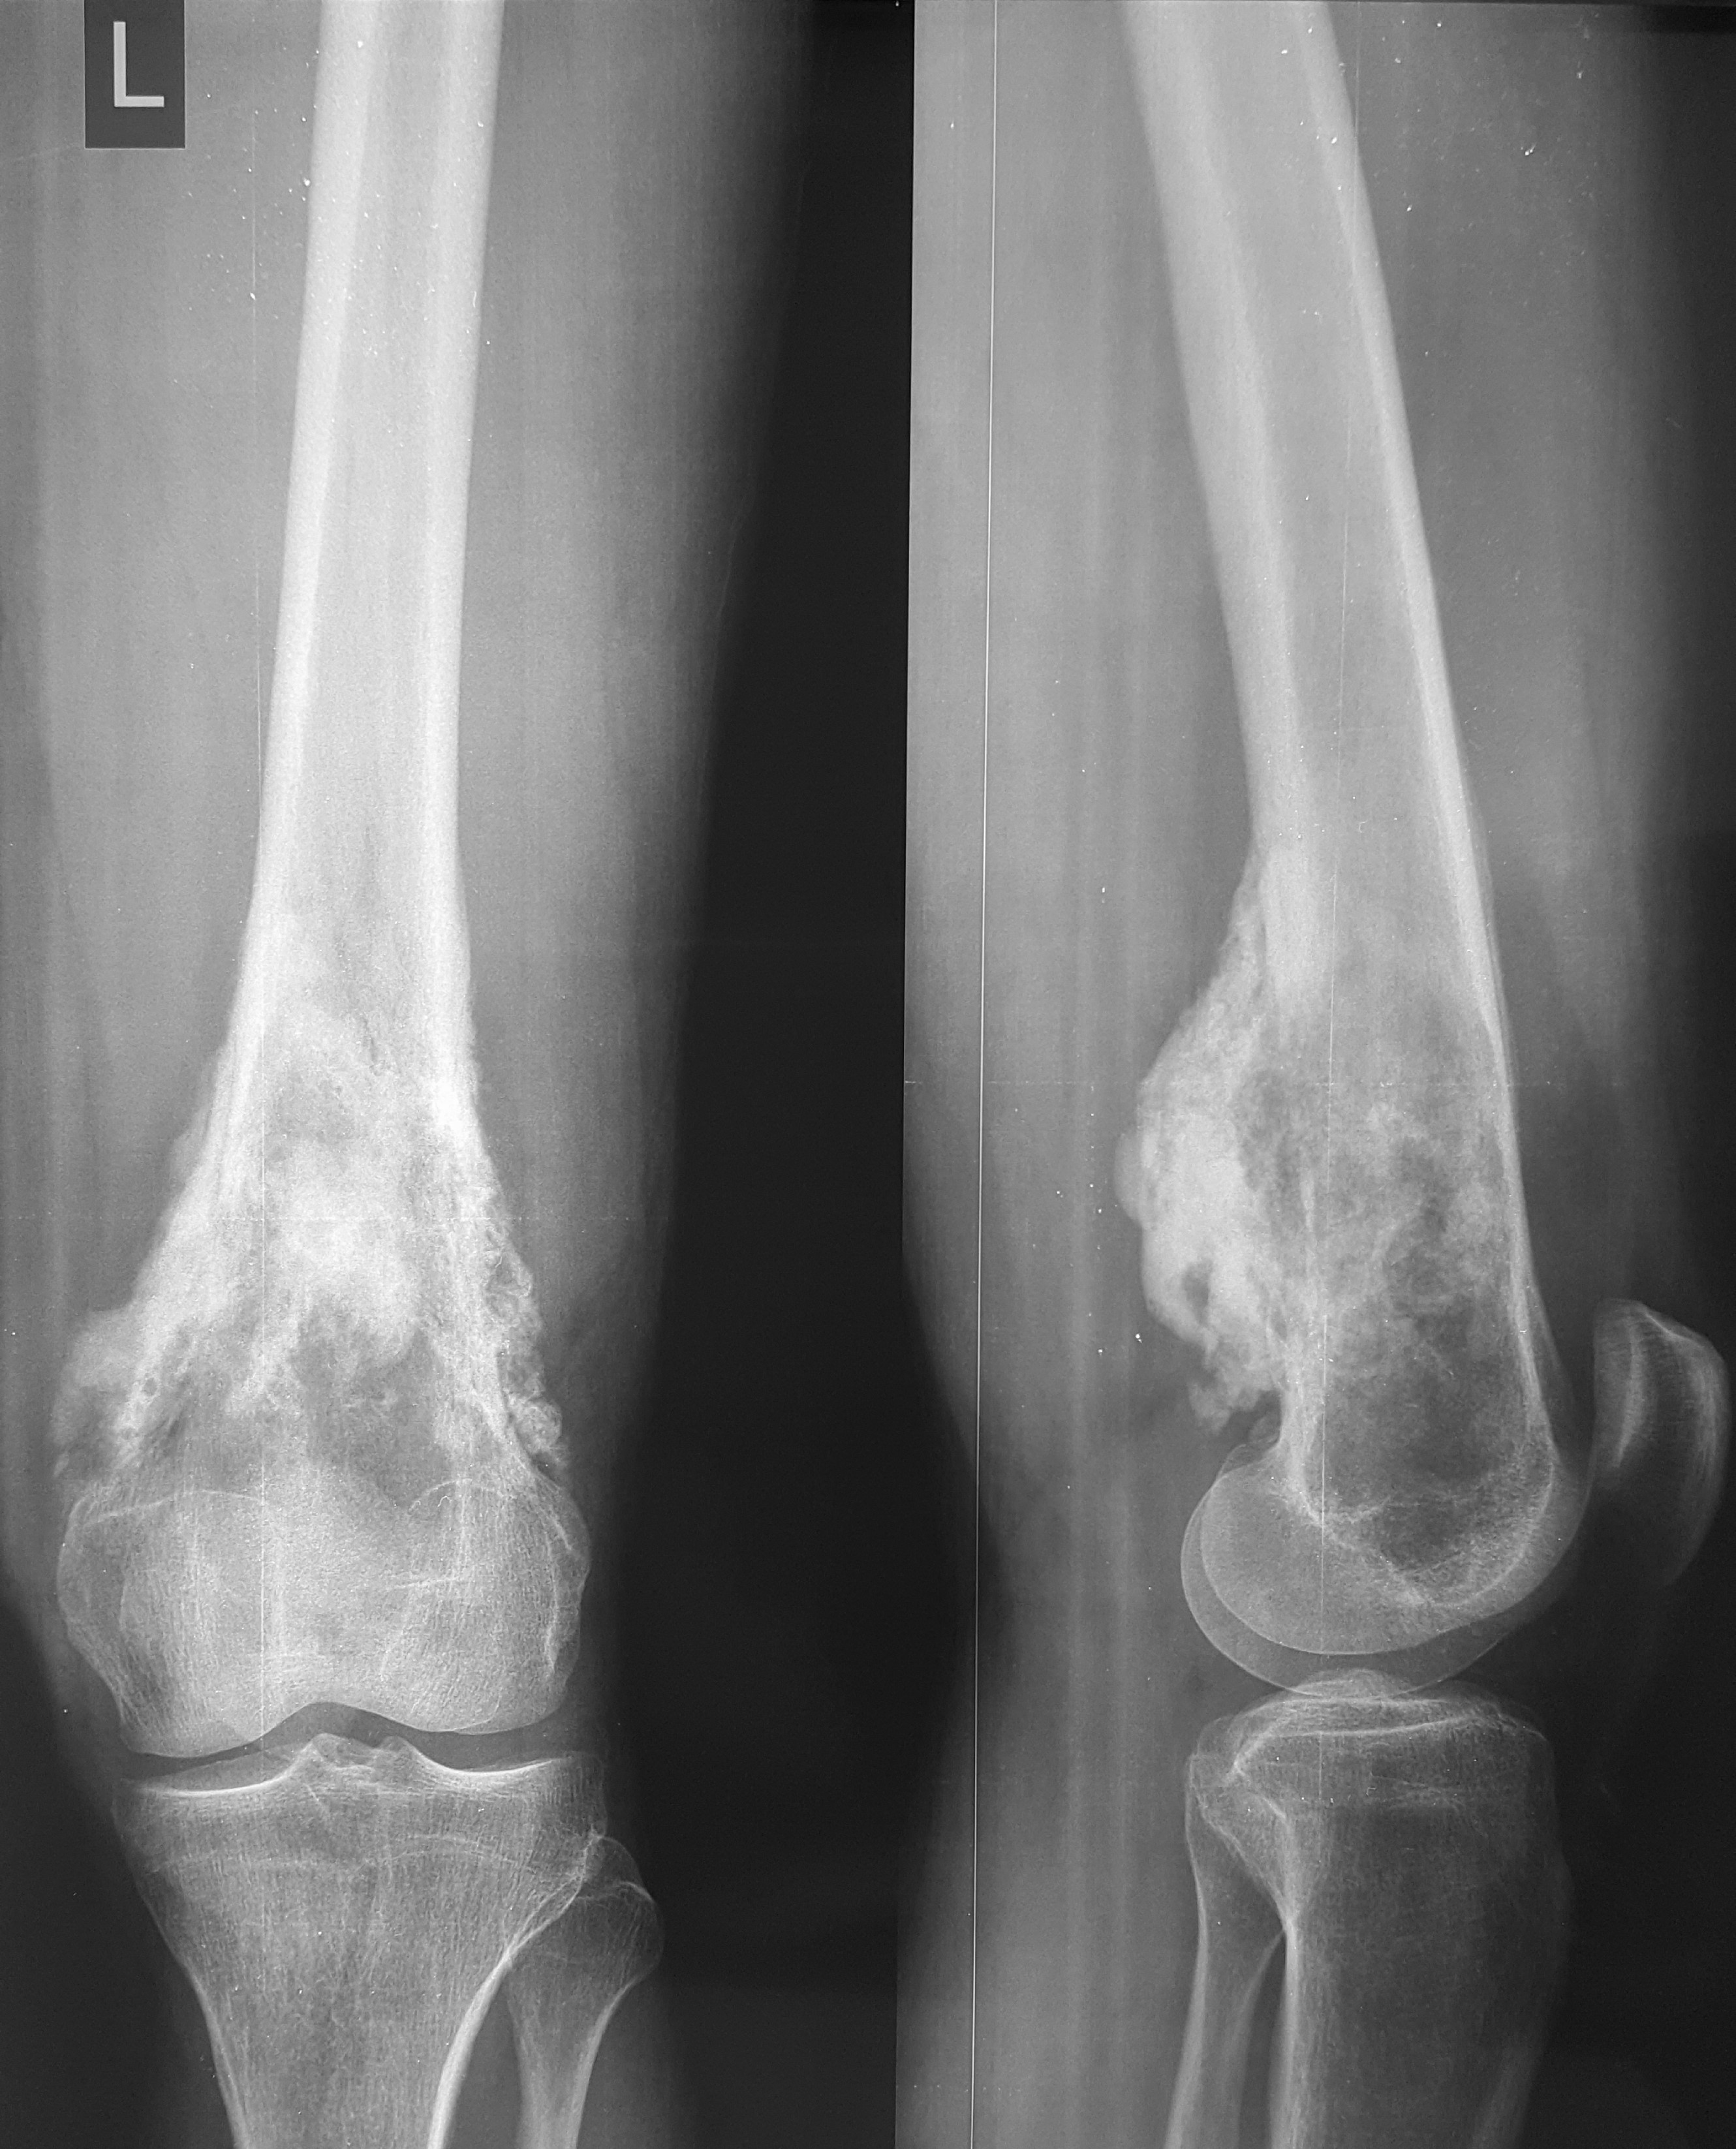

5. Хондросаркома бедренной кости

37-летний пациент обратился в клинику с жалобами на боли в области верхней трети бедра. В ходе обследования была диагностирована хондросаркома бедренной кости. Учитывая, что данный вид опухоли не поддается химиотерапии, специалисты рассмотрели два варианта операции: ампутацию, операцию с сохранением органа. С учетом нечувствительности данного варианта опухоли к лекарственному и лучевому лечению выбор стоял между проведением ампутации (которую рекомендовали в ряде зарубежных клиник в ходе телеконсультаций ввиду выраженного мягкотканного компонента) и органосохраняющим вмешательством. Произведено хирургическое лечение – сегментарная резекция бедренной кости и коленного сустава, замещение дефекта индивидуальным эндопротезом. Спустя 7 лет после операции пациент жив, местного рецидива и отдаленных метастазов заболевания не выявлено, функция оперированной конечности оценивается на «отлично».

До операции

После операции